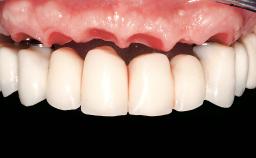

Immediate Loading of Eight Implants in the Maxilla and Six Implants in the Mandible and Final Restoration with Three-Unit and Four-Unit FDPs

Prosthesis Type FDP

SAC Level Complex

Defining Characteristics Fully edentulous upper jaw to be rehabilitated with an implant-borne fixed dental prosthesis